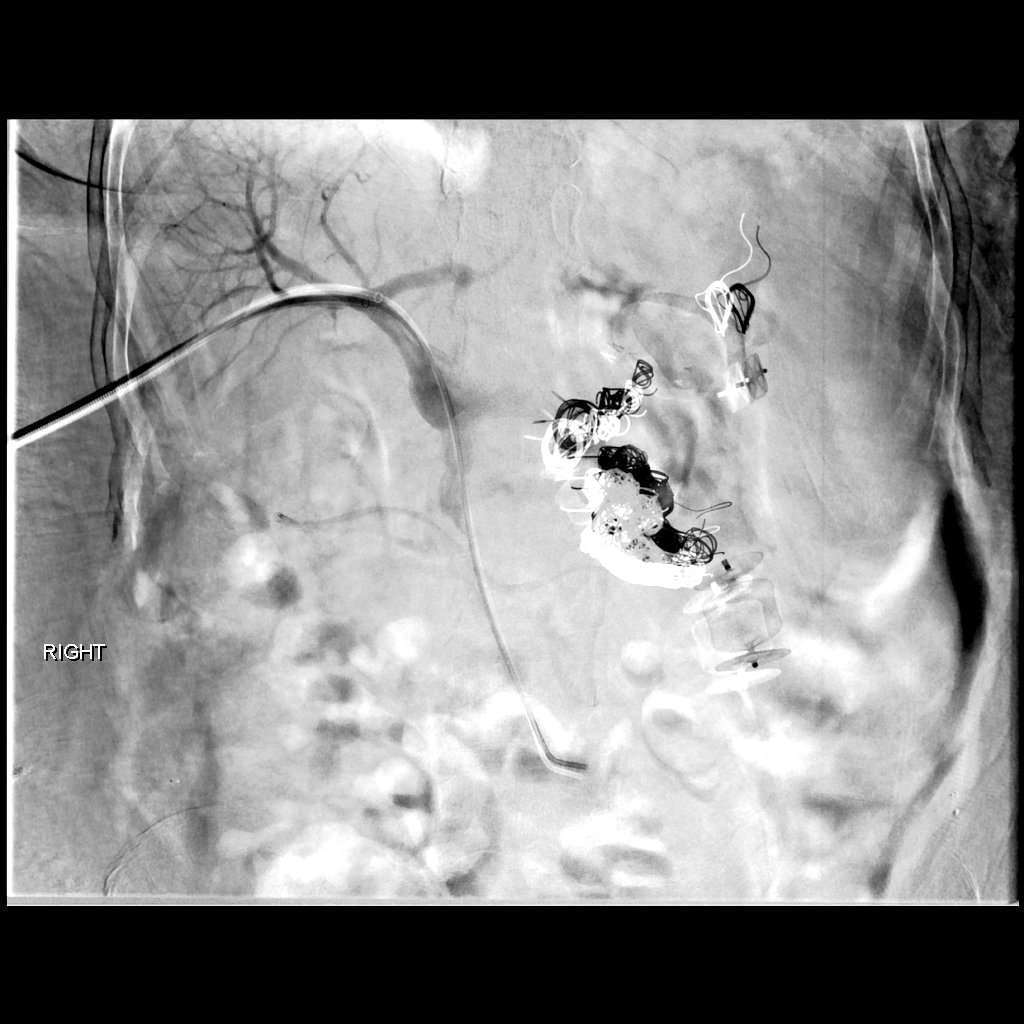

Part 2/2: 25 yo M IVDA with pulmonic valve vegetation. Successful Angiovac aspiration of 1.1cm vegetation with TEE guidance and no contrast. Vegetation positive for micrococcus luteus, antibiotics adjusted accordingly. Joseph DeMarco Gary Siskin SIR RFS #withoutascalpel #IRad

Part 2/2: 25 yo M IVDA with pulmonic valve vegetation.  Successful Angiovac aspiration of 1.1cm vegetation with TEE guidance and no contrast.  Vegetation positive for micrococcus luteus, antibiotics adjusted accordingly. <a href="/Striker9DO/">Joseph DeMarco</a> <a href="/gsiskin/">Gary Siskin</a> <a href="/SIRRFS/">SIR RFS</a> #withoutascalpel #IRad